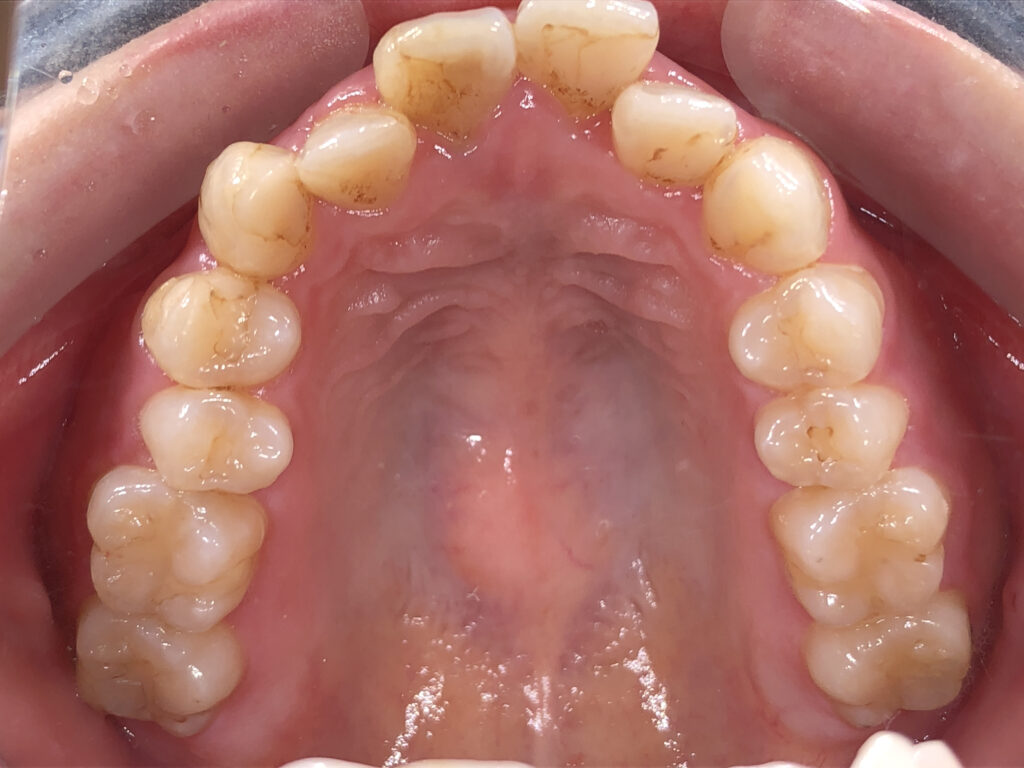

上顎

治療前